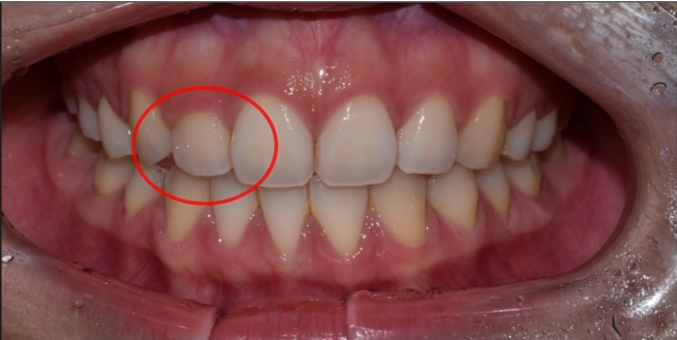

여러분이 고민하시는 작은 이빨은 왜소치(microdontia)라고 해서 기존 정상 치아보다 크기가 작은 치아를 말합니다.

대체로 측절치(두 번째 앞니, 대문니 양옆 치아)가 정상 크기보다 작은 경우가 많은데요.

다양한 왜소치 사례

대문니의 약 70~80% 정도의 비율이 측절치의 정상적인 크기라고 한다면, 이보다 훨씬 더 작은 왜소치로 형성되는 것이죠.